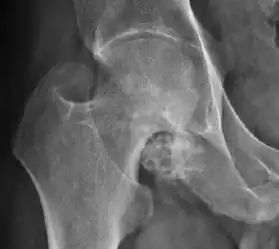

Plain radiography allows us to categorize the hip as normal or dysplastic or with impingement signs (pincer, cam, or a combination of both). Besides these, pathologic processes like osteoarthritis, inflammatory diseases, infection, or tumors can also be identified (Figure 1).[1]

Figure 1.

-

Radiography in normal hip -

X-ray in pincer impingement type of hip dysplasia -

X-ray of cam -

Hip in osteoarthritis -

Septic arthritis

X-ray in pediatrics

There are other pathological conditions that can affect the hip joint and radiographs help to make the appropriate diagnosis. Acute bacterial septic arthritis can be diagnosed by radiographs when a fast regional osteoporosis and destructive monoarticular process develops (Figure 1(f)). In case of tuberculous or brucella arthritis it is manifested as a slow progressive process, and diagnosis may be delayed.[1]

Synovial chondromatosis can be confidently diagnosed by X-ray when calcified cartilaginous chondromas are seen. However, other synovial proliferative processes, such as pigmented villonodular synovitis, require MRI for accurate diagnosis, although noncalcified synovitis can be suspected in radiographs by indirect signs, such as soft tissue swelling and/or erosions in the femoral head, femoral neck, or acetabulum (Figure 7).[1]